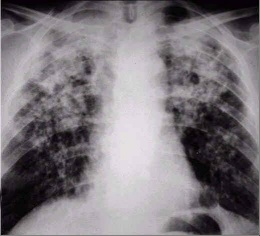

Síndrome de Caplan. Es la hinchazón (inflamación) y cicatrización de los pulmones en personas con artritis reumatoidea que han estado expuestas al polvo de las minas que contienen carbón. La enfermedad pulmonar se denomina neumoconiosis de los mineros del carbón.

El síndrome de Caplan es causado por la inhalación de polvo de las minas del carbón, lo cual causa inflamación y puede llevar al desarrollo de muchas protuberancias (nódulos) pulmonares pequeñas y a una enfermedad leve de las vías respiratorias similar al asma. Algunas personas que han estado expuestas al polvo presentan una cicatrización pulmonar severa, llamada fibrosis masiva y progresiva, que le dificulta a los pulmones el transporte de oxígeno al torrente sanguíneo. Las personas con artritis reumatoidea no parecen tener una mayor probabilidad de presentar esta complicación de la cicatrización. El síndrome de Caplan es muy poco común en los Estados Unidos.

- Radiografías de tórax

- Tomografía computarizada del tórax